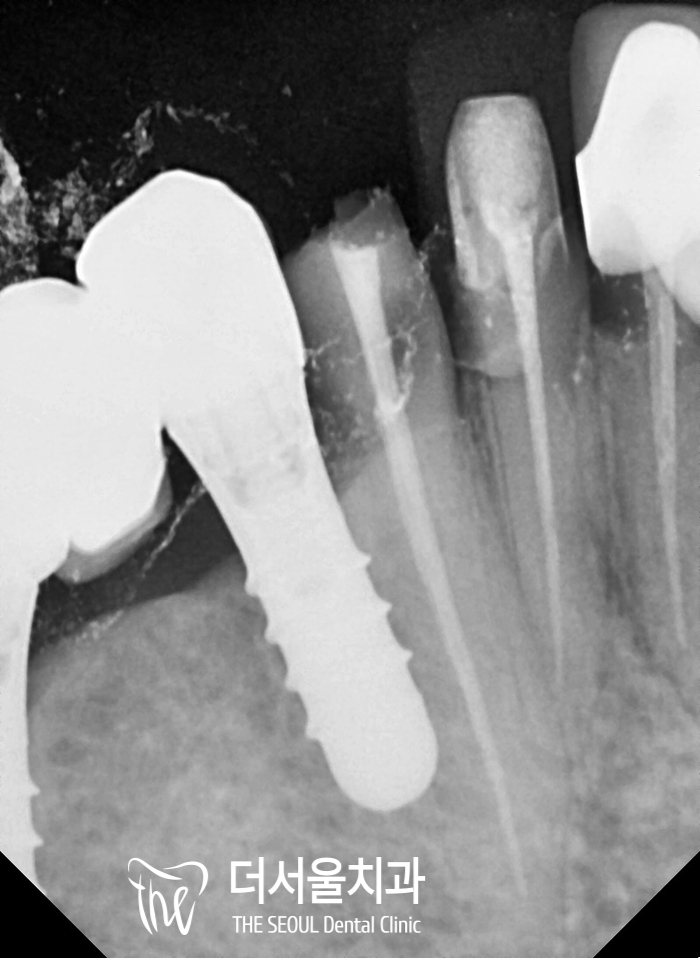

셋팅을 하기 전, 한번 더 엑스레이 촬영으로

신경치료가 된 곳에 다른 증세들이 없는지

꼼꼼히 확인을 했으며 지르코니아 재료로

만든 Crown 을 셋팅을 해드렸습니다.